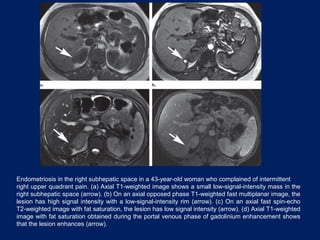

Endometriosis in the right subhepatic space in a 43-year-old woman who complained of intermittent

right upper quadrant pain. (a) Axial T1-weighted image shows a small low-signal-intensity mass in the

right subhepatic space (arrow). (b) On an axial opposed phase T1-weighted fast multiplanar image, the

lesion has high signal intensity with a low-signal-intensity rim (arrow). (c) On an axial fast spin-echo

T2-weighted image with fat saturation, the lesion has low signal intensity (arrow). (d) Axial T1-weighted

image with fat saturation obtained during the portal venous phase of gadolinium enhancement shows

that the lesion enhances (arrow).